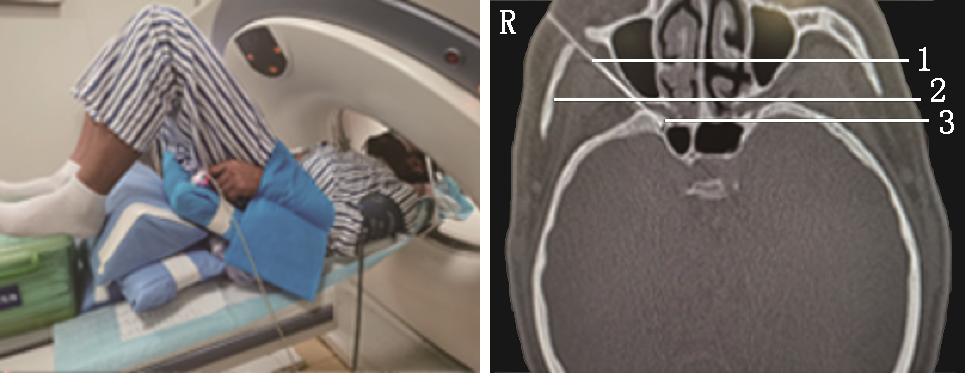

次日查房,患诉原额头部位疼痛缓解,但同侧鼻腔出现剧烈火烧样疼痛,NRS评分7分,其所诉位置位于三叉神经第二支分布区域,故行CT引导下局部麻醉经皮穿刺圆孔三叉神经第二支射频热凝术[5],穿刺顺利,针尖在圆孔外口(图5),行95 ℃,300 s射频热凝。

第2次手术术后5 d,患者诉右侧颜面部疼痛基本缓解NRS 1~2分,但出现右侧颈枕部剧烈疼痛,是颈2神经分布区域,同时原右侧额顶部疼痛复发,爆发痛NRS评分可达6分,每天发作数十次,不能忍受,要求继续治疗。与家属说明做颈2神经根射频热凝会使同侧颈枕部出现麻木,眶上神经射频热凝会使同侧额顶部麻木,患者疼痛不能忍受,强烈要求继续行射频热凝术。因此,行经皮穿刺颈2神经根射频热凝术[6]+眶上孔眶上神经射频热凝术[7]。均采用局部麻醉CT引导模式,颈2神经根射频热凝术采用侧卧体位,术前规划穿刺路线,穿刺针到达目标靶点(图6),进行射频热凝,95 ℃、300 s,后拔出穿刺针结束,转平卧体位行眶上孔眶上神经射频热凝术,穿刺针到达眶上孔内(图7),行95 ℃、300 s射频热凝。术后颈枕部及额顶部麻木,疼痛基本消失,NRS评分1~2分,有轻微右眼不自觉流泪症状,效果满意。